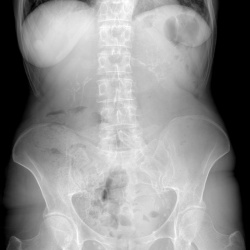

Пациентка 62г. поступает в приёмный покой больнцы в связи с болями в животе, подъёмы температуры до 38 градусов.Выставлялась болень Крона.Выполнен обзорный снимок брюшной полости.